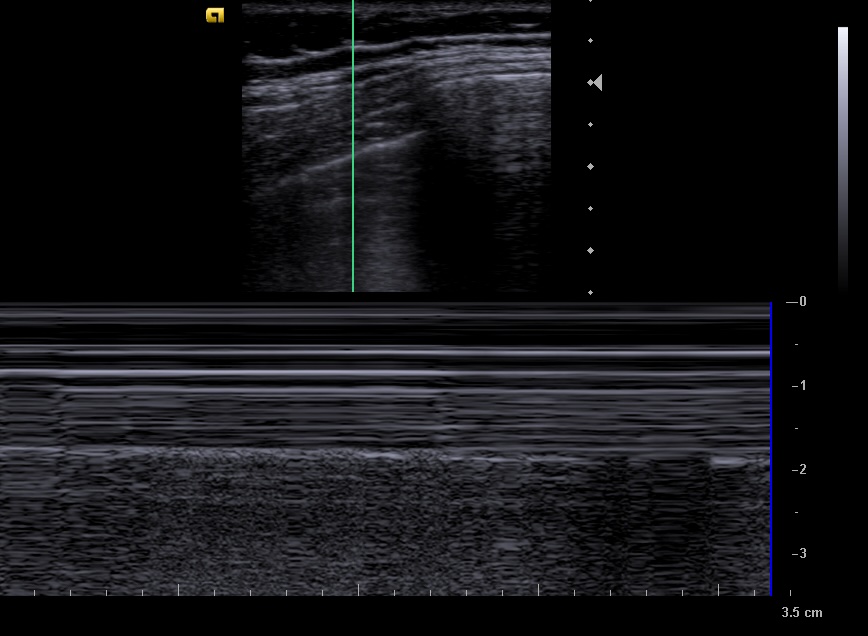

En la ecografía apreciamos en campo derecho un patrón ecográfico tisular, con líneas y puntos hiperecoicos, y algún artefacto en cola de cometa, correspondientes a broncograma aéreo.